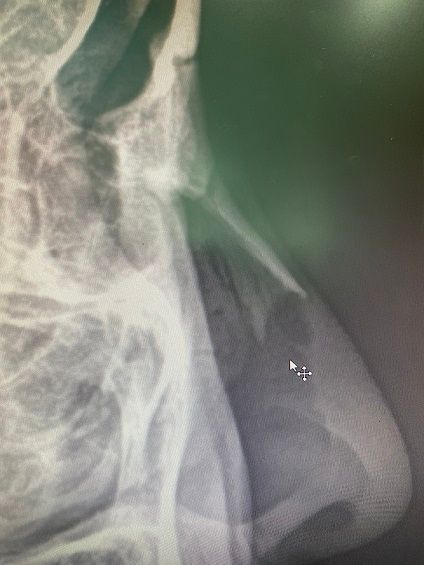

몇 일 전에 찍은 코 엑스레이 사진인데요.

코 엑스레이에 대해 궁금하시군요. 붉은색으로 표시하신 부분은 코에 존재하는 연골입니다. 뼈보다는 덜 하얗게 보이지만 분명 그 윤곽을 확인할 수 있습니다.

해당부분은 연골로 칼슘등이 있고 이또한 고체성분이기 때문에 뼈보다는 옅은 흰색으로 보일 수 있습니다